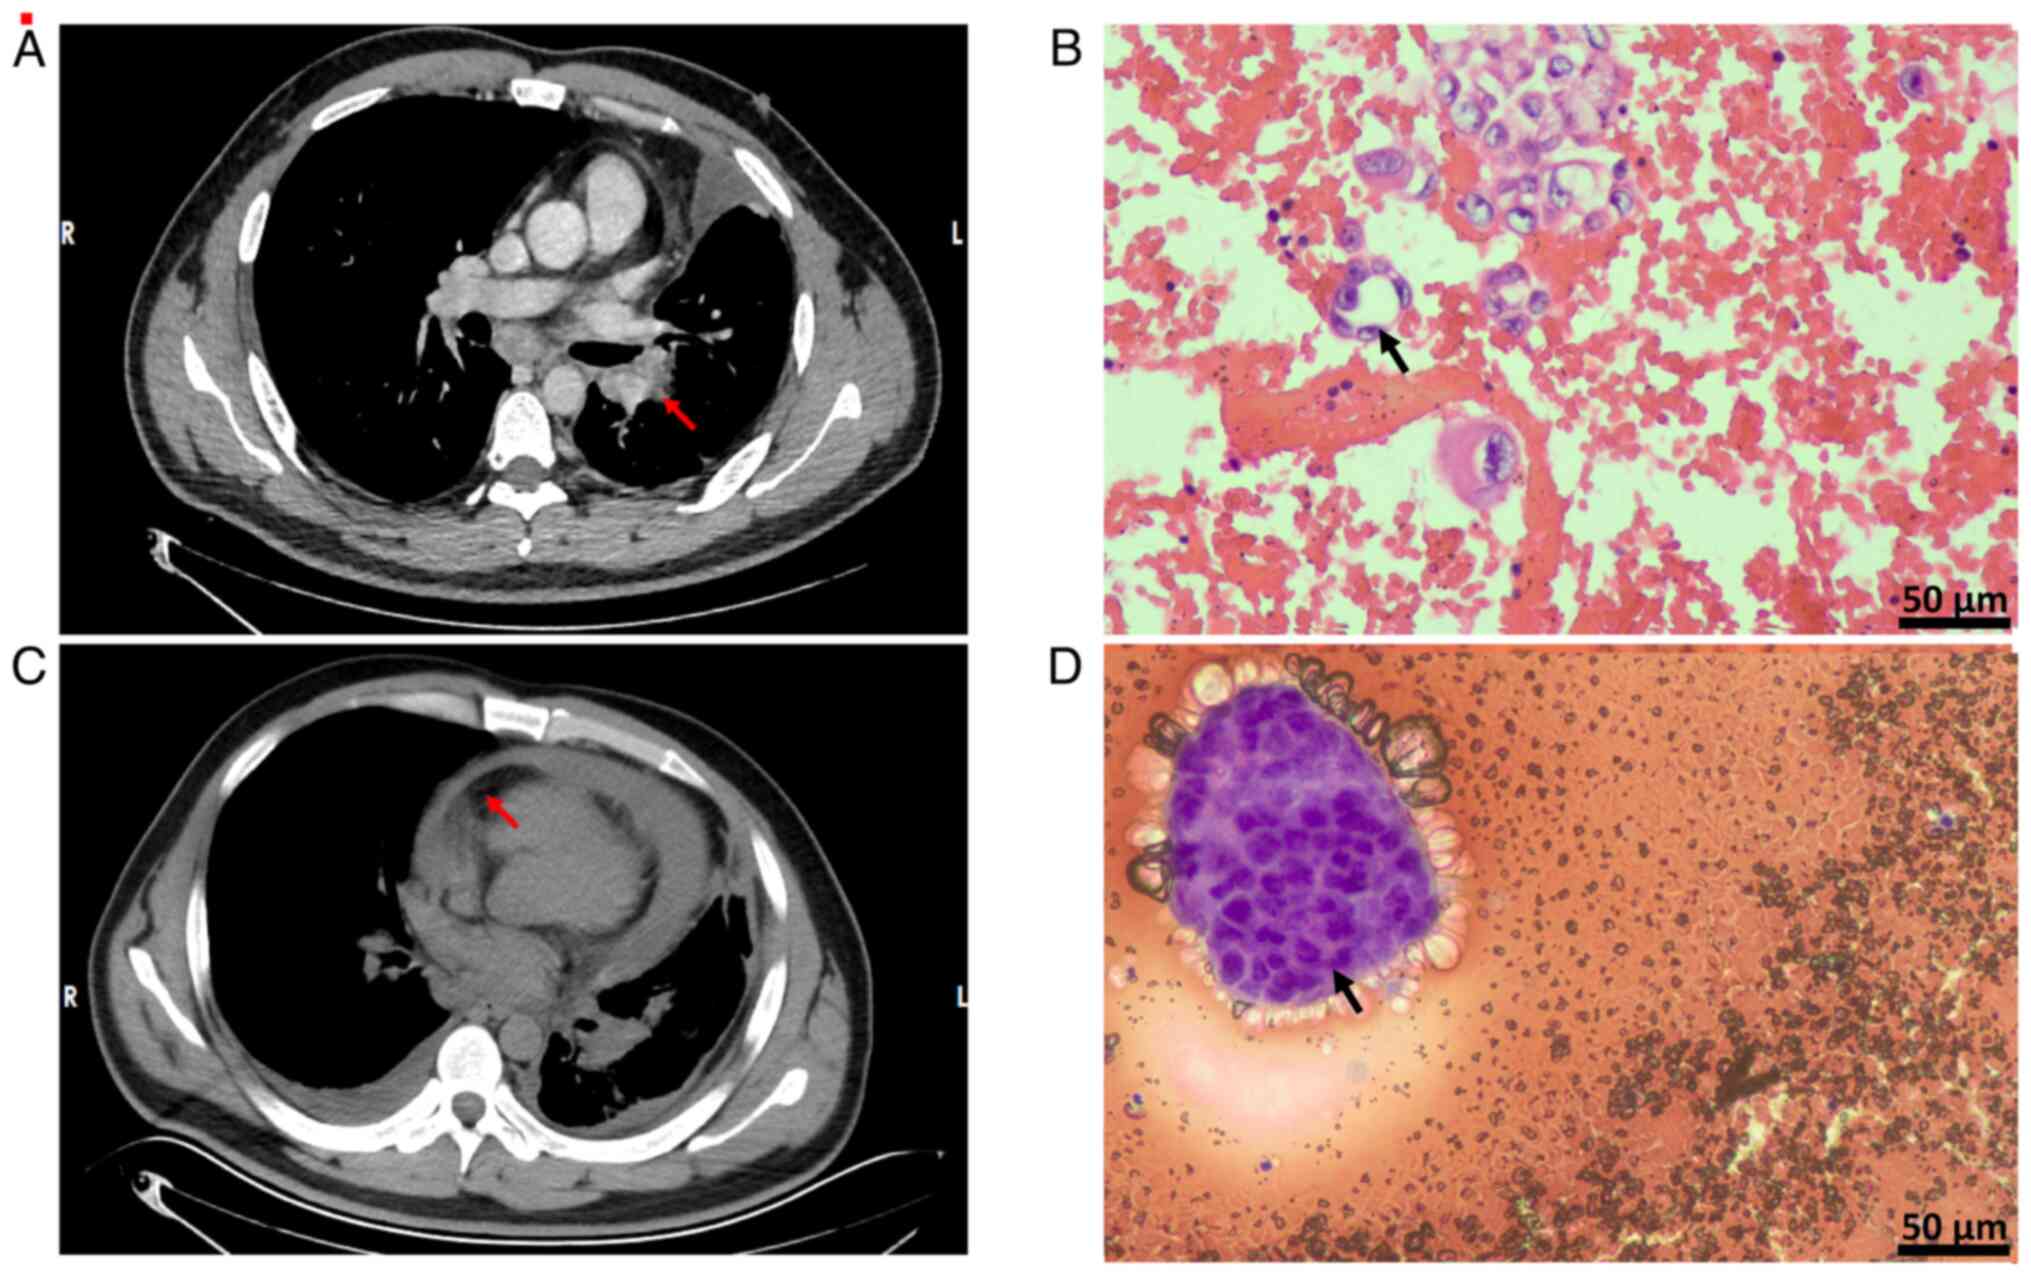

The patient was admitted to the First People's Hospital of Suining in October 2024 due to pleural effusion. Lung adenocarcinoma cells were identified in the exfoliated cells from the pleural effusion, which led to a diagnosis of a malignant tumor in the upper lobe of the left lung, classified as adenocarcinoma T3N2M1a at IVA stage (16) (Fig. 1A and B). On admission, according to the Khorana scoring scale (17), the VTE score of the patient was classified as low-risk. Additionally, malignant pericardial effusion (MPE) was diagnosed at the First People's Hospital of Suining in October 2024 (Fig. 1C and D), which prompted the performance of pericardiocentesis and catheter drainage. A week before presentation in December 2024, color ultrasound examinations of the lower extremity veins and the internal jugular vein demonstrated thrombosis in the popliteal vein, posterior tibial vein, peroneal vein and right internal jugular vein. Following discharge, the patient was prescribed rivaroxaban at a dose of 10 mg twice daily for anticoagulation for 3 months, with dose and frequency adjusted based on lower extremity venous ultrasound review.

Chest CT revealing a lung mass and

pericardial effusion, which was confirmed by H&E staining for

lung adenocarcinoma and pericardial metastases. (A)

Contrast-enhanced chest CT identified a pulmonary mass in the left

upper lobe, indicated by the red arrow, which exhibited

characteristic neoplastic morphology. (B) Analysis via H&E

staining of the pleural effusion confirmed metastatic lung

adenocarcinoma. Tumor cells are indicated by the black arrow

(H&E staining; scale bar, 50 µm). (C) Chest CT demonstrated

pericardial effusion. The red arrow indicates thrombosis of the

splenic artery. (D) H&E staining of the pericardial effusion

also revealed lung adenocarcinoma cells. Tumor cells are indicated

by the black arrow (H&E staining; scale bar, 50 µm).

Figure 1.

Chest CT revealing a lung mass and pericardial effusion, which was confirmed by H&E staining for lung adenocarcinoma and pericardial metastases. (A) Contrast-enhanced chest CT identified a pulmonary mass in the left upper lobe, indicated by the red arrow, which exhibited characteristic neoplastic morphology. (B) Analysis via H&E staining of the pleural effusion confirmed metastatic lung adenocarcinoma. Tumor cells are indicated by the black arrow (H&E staining; scale bar, 50 µm). (C) Chest CT demonstrated pericardial effusion. The red arrow indicates thrombosis of the splenic artery. (D) H&E staining of the pericardial effusion also revealed lung adenocarcinoma cells. Tumor cells are indicated by the black arrow (H&E staining; scale bar, 50 µm).

H&E staining and immunohistochemistry

Histological analysis was performed on tissue sections fixed in 10% neutral buffered formalin at room temperature for 24 h. The tissue was processed, embedded in paraffin and sectioned at a thickness of 5 µm. Sections were stained with hematoxylin and eosin for 5 min at room temperature, following standard protocols. The slides were examined using a light microscope (Leica DM3000; Leica Microsystems GmbH) at a magnification of ×400. After H&E staining, the following results were observed: Tumor cells were found in the pleural fluid, with an enlarged nucleoplasm ratio, deviated nuclei, pronounced nucleoli and sparse vacuolated cytoplasm (Fig. 1B). Immunohistochemistry (data were obtained from medical records and are not shown) showed the following: Transcriptional intermediary factor 1 (+); NapsinA (+); P40 (−); cytokeratin 5/6 (−); cytokeratin (+); calretinin mesothelium (+); desmin mesothelium (+); Wilms' tumor protein 1 (−); and Ki67-positive rate, ~10%.

Pericardial effusion analysis

Adenocarcinoma was identified via pericardial effusion analysis.

Histological analysis was performed on tissue sections fixed in 10% neutral buffered formalin at room temperature for 24 h. The tissue was processed, embedded in paraffin and sectioned at a thickness of 5 µm. Sections were stained with hematoxylin and eosin for 5 min at room temperature, following standard protocols. The slides were examined using a light microscope (Leica DM3000; Leica Microsystems GmbH) at a magnification of ×400. After H&E staining, the following results were observed: Tumor cells were found in the pericardial effusion cell block, the tumor cells were arranged in an adenoidal/papillary pattern with deeply stained, enlarged nuclei with prominent nucleoli and cytoplasm containing mucus vacuoles (Fig. 1D). Immunohistochemistry (data were obtained from medical records and are not shown) revealed the following: Cytokeratin 7 (+); thyroid transcription factor 1 (weak +); NapsinA (+); p40 (−); and Wilms' tumor protein (−).